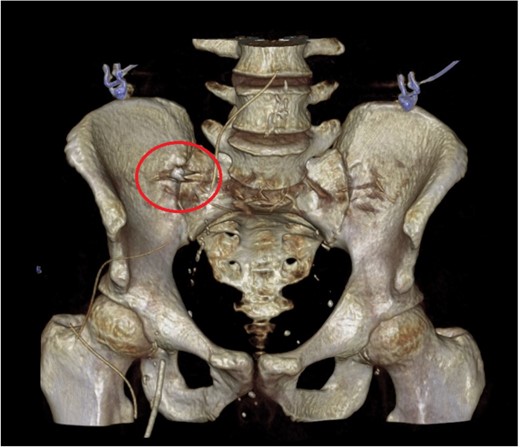

A 52-year-old gentleman who presented to the Emergency Department in septic shock with right sided abdominal pain. He suffered a witnessed cardiac arrest prompting immediate cardiopulmonary resuscitation (CPR) with return of spontaneous circulation (ROSC) after 10 minutes. Physiologic resuscitation was commenced, and he was started on broad spectrum intravenous antibiotics with cefuroxime and metronidazole, as per local guidelines. Following intubation and ventilation, he underwent a computer tomography (CT) scan of the abdomen which revealed moderate volume of free fluid with locules of gas within the pelvis suggesting a hollow viscus perforation. A calcified structure was identified within the appendix raising the possibility of a foreign body causing perforated appendicitis. On reconstructed slices, the appearance was that of a tooth (Figs 1 and 2).

Axial and coronal CT slices showing radiopaque object in the right lower abdominal quadrant.